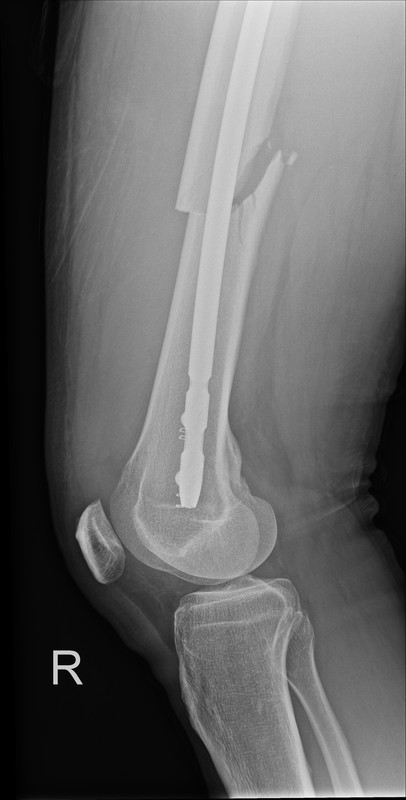

Der Oberschenkelknochen war gebrochen.

In einer "Not"-OP (KH Zams/Tirol) wurde ein Nagel mit 3 Schrauben eingebracht, um den Bruch zu stabilisieren.

Leider sitzen die Knochenenden nicht regelrecht aufeinander.

Der empfahl, dass die Schrauben und der Nagel wieder raus sollen, der Knochen von innen weiter aufgefräst wird, um einen dicker Nagel (14mm) einzubringen.

Derzeit ist ein 11mm Nagel drin. Gleichzeitig soll die "wenig" gebildende Knochenmasse wieder rausgenommen werden (zusätzlicher, seitlicher Schnitt).

Die Bruch teilt sich auf: 2/3tel oben, 1/3tel unten.

Die Bruchstelle soll wohl auch deshalb schlecht heilen, weil

a.) der Spalt zu groß ist und

b.) der Knochen an dieser Stelle schlecht durchblutet ist und somit wenig Knochenheilung (Kallus) stattfinden kann.

Alternativ werden die beiden knienahen Verriegelungsschrauben entfernt und von vorne eine Schraube in das dort befindliche Langloch verschraubt, um mehr Bewegung/Kompression/Mobilisierung zu erzeugen.